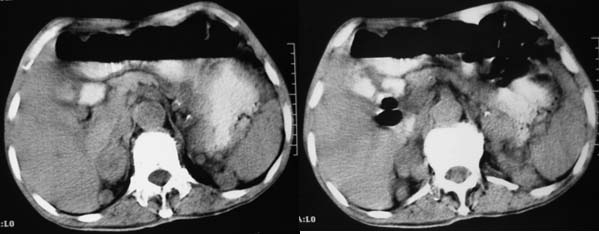

上腹部横断图象显示:心包,胃体小弯侧,肾等器官周围以及肠系膜腹膜后多发的大小不等的小结节样软组织密度影,部分境界不清,未见明显钙化.如此广泛的小结节样影,我认为首先考虑淋巴结肿大.能够引起淋巴结肿大的最常见的原因为:1.炎症(结核常见);2.转移;3.淋巴瘤.其中淋巴结结核不同程度可见钙化,而且这么大范围少见,暂不考虑.

肝胃间隙,双侧肾周间隙,腹主动脉旁类圆形软组织结节影,首先考虑是增大的淋巴结。

综合上述表现及临床,首先考虑右侧肾上腺及腹腔,腹膜后淋巴结转移.其次考虑淋巴瘤.

双侧肾及右肾可见肿块影伴心包周围腹腔腹膜后腹主动脉旁多发肿大淋巴结。

印象:1、考虑转移性质,积极寻找原发病灶注意与淋巴瘤鉴别。